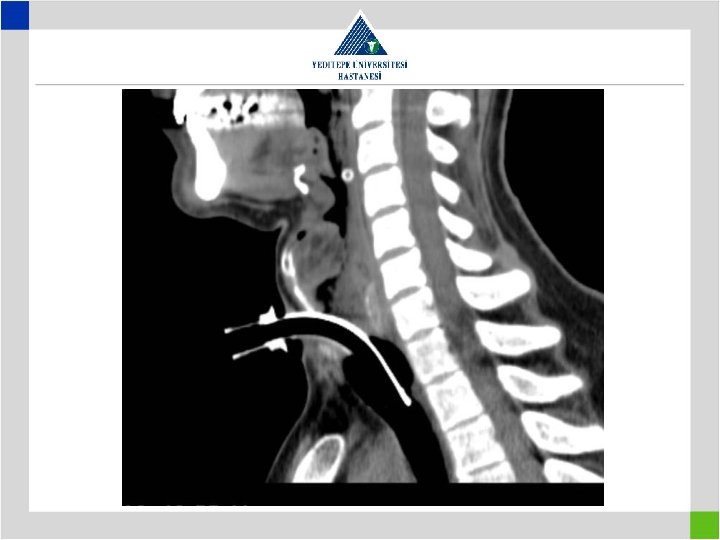

Diagnosis • Stenotic segment calculation to be correct • CT image in supine position may falsly indicate a preglottic stenosis – Overresection – increased anastomotic tension – restenosis • Pediatric trachea tolerates the tension poorly in comparison with adults – Insufficient resection – remaining fibrosis – restenosis